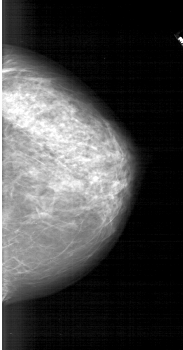

A_1744_1.RIGHT_MLO

RIGHT_MLO LINES 6406 PIXELS_PER_LINE 3361 BITS_PER_PIXEL 12 RESOLUTION 43.5 NON_OVERLAY